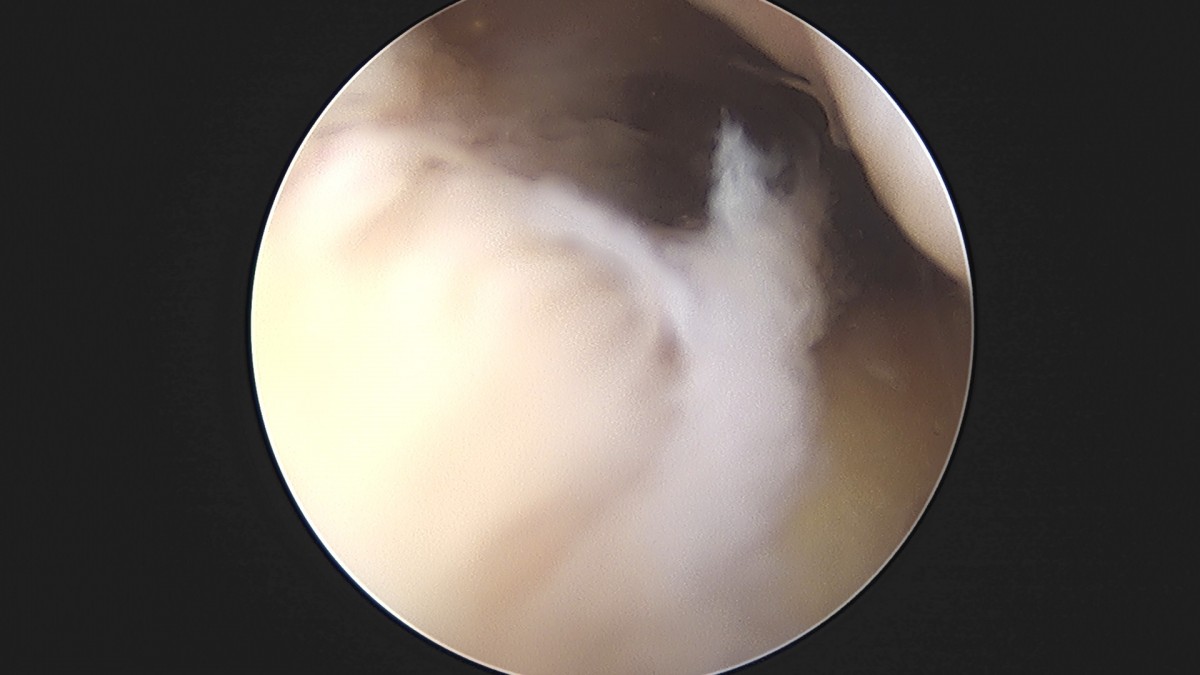

이재상원장님 무릎 반월상 연골판 절제술 최용O 환자

작성자 최고관리자 댓글 0건 조회 379회 작성일 25-09-16 15:57